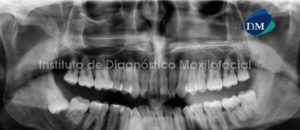

Paciente de sexo femenino y de 38 años de edad, es referida al Instituto de Diagnóstico Maxilofacial para la evaluación de un proceso infeccioso en el lado derecho del maxilar inferior.